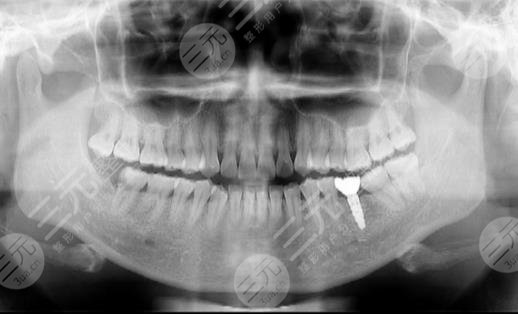

到醫(yī)院進行面診的時候,醫(yī)生先讓我咬了牙齒的模型,然后又拍了牙片,選擇了牙齒的種植體,一星期之后,我來到了醫(yī)院進行種植牙。整個種植牙的過程是很快的,而且因為打了局部mz也沒有任何的感覺。大家現在可以看到我的種植牙是十分成功的,而且看上去十分的潔白,跟周圍的牙齒形成了鮮明的對比。